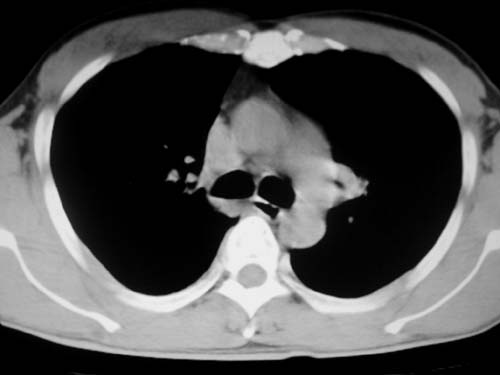

标题: CT19540: 31岁。自述结核性胸水治疗两个月后,在外院拍x线发 [打印本页]

标题: CT19540: 31岁。自述结核性胸水治疗两个月后,在外院拍x线发

右侧胸壁结节状软组织影伴相应肺叶内受侵,伴右侧胸腔积液。考虑:结核性可能大。

以下是引用王显瑞在2009-4-23 8:38:00的发言:[br]右侧胸壁结节状软组织影伴相应肺叶内受侵,伴右侧胸腔积液。考虑:结核性可能大。

支持 右侧胸壁结节状软组织影伴相应肺叶内受侵,伴右侧胸腔积液。考虑:结核性可能大。

右侧胸壁结节状软组织影伴相应肺叶内受侵,伴右侧胸腔积液,结合临床,首先考虑结核。

考虑结核性胸膜炎,胸膜肥厚,不除外胸膜间皮瘤可能,建议复查。

1)考虑右侧结核性胸膜结节。2)右侧胸膜增厚+包裹性胸腔积液。